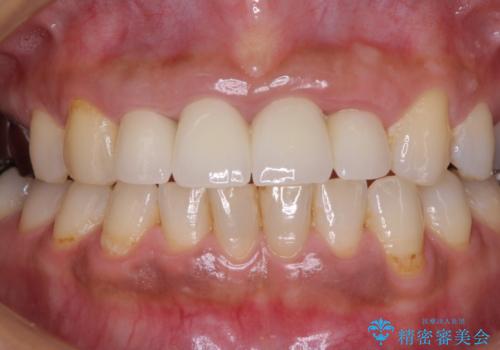

汚れた仮歯が気になる 前歯のオールセラミッククラウン

- 地元の歯科医院にて前歯4歯を仮歯に替えたものの、汚れていることが気になるとのことで来院された患者様です。

不適な仮歯の影響で歯肉が腫れていたため、新しい仮歯に替えた後に歯肉の腫れが引くのを待ち、オールセラミッククラウンにて補綴することとしました。

仮歯を変えたことで歯肉の腫れは引き、根管治療も功を奏して膿の出口はきれいに消退しました。